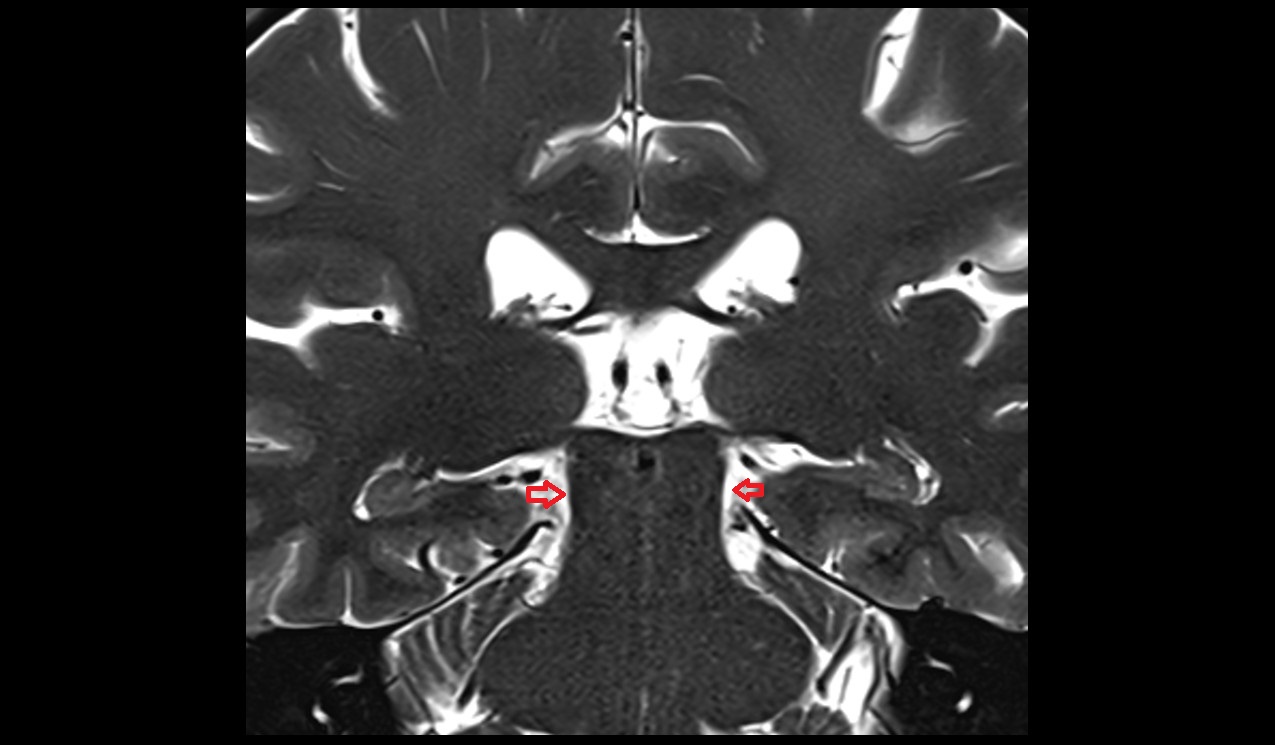

- Lateral aperture of fourth ventricle (foramen of Luschka)

- Lateral aperture of the fourth ventricle

- Lateral recess fourth ventricle

- Fourth ventricle

- Flocculus